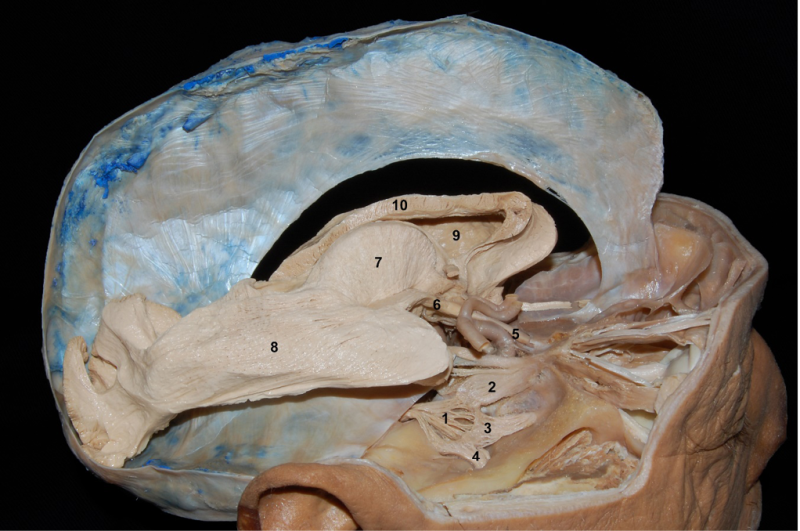

The afferent fibres of the sensory receptors are grouped into three peripheral nerves, which are the ophthalmic (V1), maxillary (V2) and mandibular (V3) (Figure 1). The neuronal bodies of the trigeminal primary afferent fibres are contained in the semilunar ganglion or Gasser?s ganglion, which is located in an excavation of the apex of the pons surrounded by the meningeal coverings, forming the so-called cavum of Meckel (Figure 1). Behind the ganglion is the trigeminal cistern, which contains cerebrospinal fluid; this cistern communicates with the cisterns of the posterior fossa via the so-called porus trigemini. Gasser?s ganglion is somatotopically organised medially to laterally 7, so that the neurons of the ophthalmic branch are located anteromedially, those of the mandibular branch posterolaterally and those of the maxillary branch in the middle of the other two. Although the ophthalmic and maxillary branches are well separated, there is some overlap between the maxillary and mandibular branches 8.

The trigeminal root runs from Gasser?s ganglion to the pons; it consists of a major or sensory portion, a minor or motor portion and an intermediate or accessory portion 8 ( Figure 1).

1. Ganglion of Gasser.

2. Ophthalmic branch (V1)

3. Maxillary branch (V2).

4. Mandibular branch (V).

5. Optic nerve.

6. Optic tract

7. Thalamus.

8. Optical radiation.

9. Frontal horn of the lateral ventricle.

10. Corpus callosum